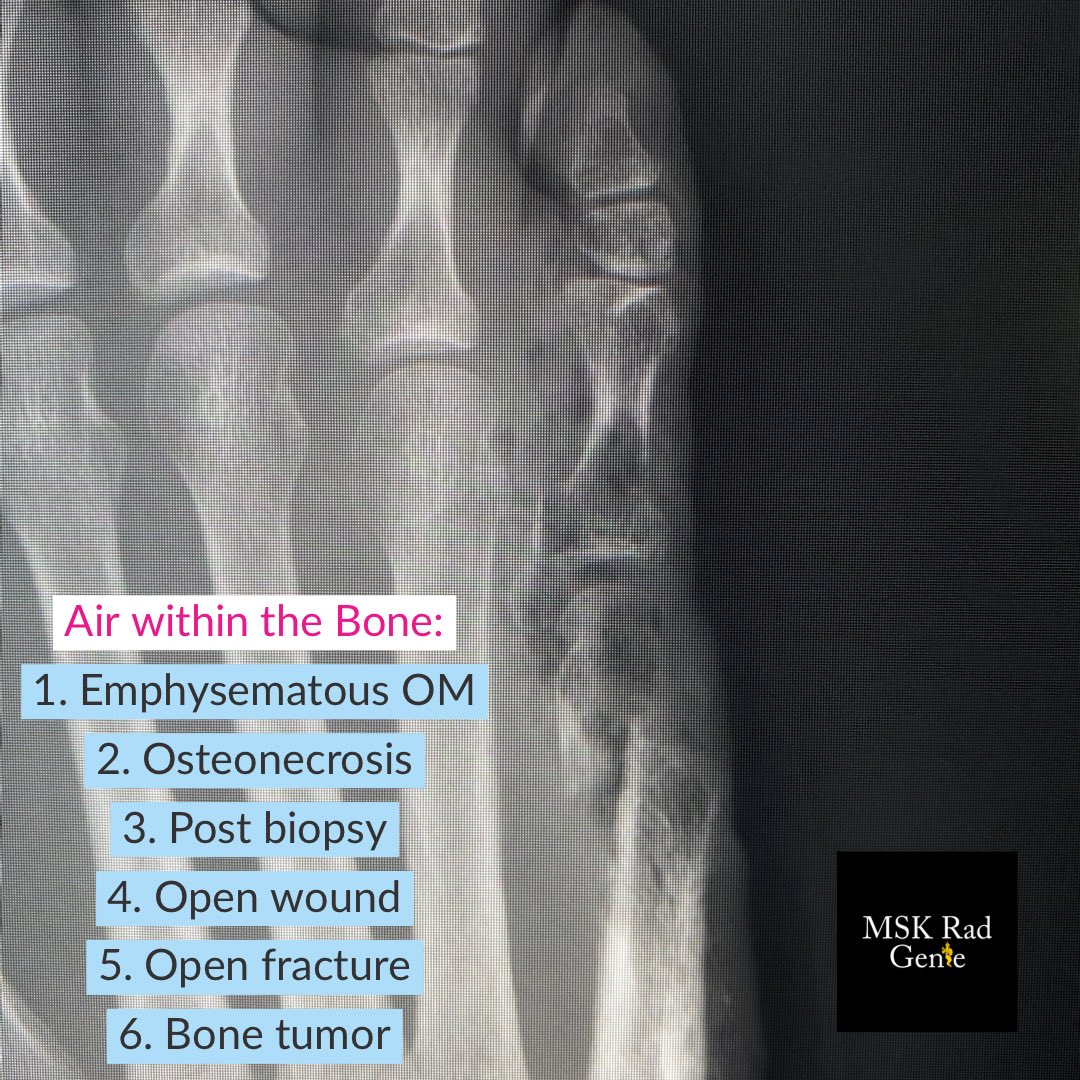

Not all air within the bone is caused by infection, although that was the case in this diabetic patient with early necrotizing fasciitis and emphysematous osteomyelitis.

#RadRes#MSKRadpic.twitter.com/ydnxzHnn3P